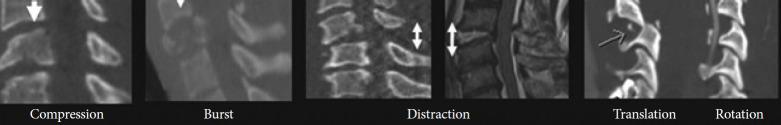

To formulate specific guidelines for the recommendation of subaxial cervical spine injuries concerning classification, management, posttraumatic locked facets and vertebral artery injury. Computerized literature was searched on PubMed and google scholar database from 2009 to 2020. For classification, keywords "Sub Axial Cervical Spine Classification," resulting in 22 articles related to subaxial cervical spine injury classification system (SLICS) system and 11 articles related to AO (Arbeitsgemeinschaft für Osteosynthesefragen, German for "Association for the Study of Internal Fixation") Spine system. The literature search yielded 210 and 78 articles on "management of subaxial cervical spine injuries" and the role of "SLICS" and "AO Spine" respectively. Keywords "management of traumatic facet locks" were searched and closed reduction, traction, approaches and techniques were studied. "Vertebral artery injury and cervical fracture" exhibited 2,328 references from the last 15 years. The objective was to identify the appropriate diagnostic tests and optimal treatment. Up-to-date information was reviewed, and statements were produced to reach a consensus in 2 separate consensus meetings of World Federation of Neurosurgical Societies (WFNS) Spine Committee. The statements were voted and reached a positive or negative consensus using Delphi method. Based on the most relevant literature, panelists in Moscow consensus meeting conducted in May 2019 drafted the statements, and after a preliminary voting session, the consensus was identified on various statements. Another meeting was conducted at Peshawar in November 2019, where in addition to previous statements, few other statements were discussed and voted. Specific recommendations were then formulated guiding classification, management, locked facets and vertebral artery injuries. This review summarizes the WFNS Spine Committee recommendations on subaxial cervical spine injuries.

制定关于下颈椎损伤的分类、管理、创伤后小关节交锁和椎动脉损伤推荐的具体指南。在PubMed和谷歌学术数据库中检索2009年至2020年的计算机化文献。对于分类,关键词“下颈椎分类”,检索到22篇与下颈椎损伤分类系统(SLICS)相关的文章以及11篇与AO(德语“骨内固定研究协会”,即“内固定研究协会”)脊柱系统相关的文章。文献检索分别产生了210篇和78篇关于“下颈椎损伤的管理”以及“SLICS”和“AO脊柱”作用的文章。检索关键词“创伤性小关节交锁的管理”,并研究了闭合复位、牵引、入路和技术。“椎动脉损伤与颈椎骨折”在过去15年中有2328条参考文献。目的是确定合适的诊断测试和最佳治疗方法。回顾了最新信息,并在世界神经外科协会联合会(WFNS)脊柱委员会的2次单独共识会议上达成共识声明。这些声明采用德尔菲法进行投票,并达成肯定或否定的共识。基于最相关的文献,2019年5月在莫斯科举行的共识会议的专家小组成员起草了声明,在初步投票会议后,就各项声明达成了共识。2019年11月在白沙瓦举行了另一次会议,除了之前的声明外,还讨论并投票了其他一些声明。随后制定了关于分类、管理、小关节交锁和椎动脉损伤的具体建议。本综述总结了WFNS脊柱委员会关于下颈椎损伤的建议。